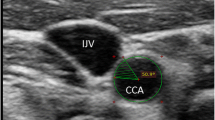

After at least 15 min of resting, hemodynamic variables were measured in supine position. Heart rate (via electrocardiogram) and blood pressure (via oscillometric method) were measured with a vascular testing device (form PWV/ABI; Omron Colin, Kyoto, Japan). Carotid arterial pressure was recorded using an applanation tonometry probe incorporating a high-fidelity strain-gauge transducer (SPT-301, Millar Instruments, Houston, TX, USA) on the left common carotid artery [12]. The pressure signal obtained by tonometry was calibrated by equilibrating the carotid mean arterial and diastolic blood pressures to the brachial mean and diastolic blood pressure measured by an oscillometric device because the baseline levels of carotid blood pressure are subject to hold-down forces [13]. Lumen diameter (from the intima of the far wall the media-adventitia of the near wall) and intima-media thickness (IMT) of carotid artery was evaluated B-mode longitudinal ultrasound images of the right common carotid artery via a duplex ultrasound machine equipped with a high-resolution (10 MHz) linear transducer (SonoSite180PLUS; SonoSite Inc., Bothell, WA, USA). Video clips of carotid arterial pulsation (more than ten beats) were stored as AVI files at 30 flames/s of sampling rate in a personal computer (Precision T5500, Dell Inc., Kawasaki, Japan), and analyzed with image-analysis software (ImageJ 1.48v, NIH, USA). Average diameter in the region of interest (approximately 1 cm × 1 cm square around 1–2 cm proximal to the bifurcation) was computed each flame, and then peak and minimum diameters were extracted in every cardiac cycle. More than five measurements of peak and minimum diameters were averaged and reported, respectively. IMT was measured at end-diastole. To characterize Windkessel function as comprehensively as possible, distensibility coefficient and β-stiffness index (an index of distensibility adjusted for distending pressure) were obtained by the following equations [14, 15]:

Blood flow velocity (BFV) measurements were performed by the Doppler method with the insonation angle <60°. The peak (systolic), minimum (diastolic), pulsatile (peak minus minimum), and mean (time-averaged) BFV were reported as averaged values calculated from successive 7–10 beats of Doppler envelopes. Furthermore, pulsatile BFV was normalized by mean BFV.